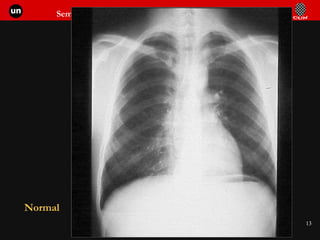

Normal

Patrón de vascularización pulmonar normal Distribución vascular simétrica Más abundante y de mayor calibre en bases Hilio izquierdo algo más alto que el derecho.

Vascularización normal